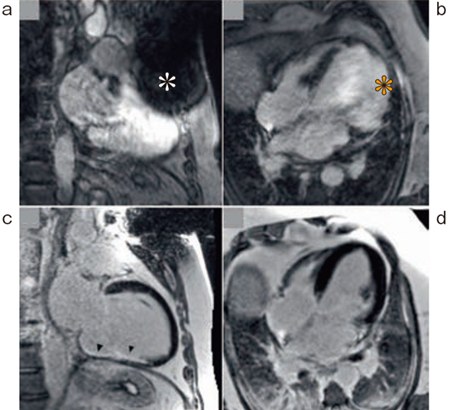

図3 High Bandwidth Inversion Recovery LGE

a,b:従来のLGE シーケンス

c,d:High Bandwidth Inversion Recovery LGE シーケンス

磁化率アーチファクトによる信号欠損(*),異常信号(*)が低減できている。

(参考文献7)より引用転載)